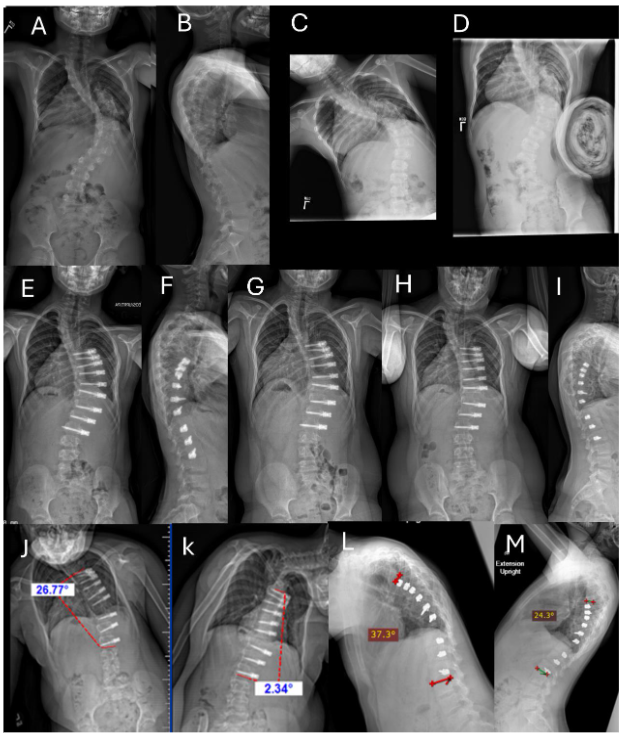

Preoperative coronal curve measurements averaged 81° (range 58 to 100°), with an average preoperative flexibility of 51% (range 21 to 71%). The first erect postoperative assessment demonstrated an average curve reduction to 33° (range 16 to 66°), translating to an average correction of 58% (range 23 to 78%). Instrumented segments showed an average reduction to 27° (range 6 to 46°) with an average correction percentage of 66% (range 47 to 91%). The most recent postoperative measurements indicated further improvement, with coronal curve angles averaging 23° (range -15 to 68°) in the instrumented segments for an average correction of 75% (range 30 to 123%). Measurement of the maximum coronal curve angle is shown in Table 1 and averaged only about 8° less correction. A case example is seen in Figure 1.

3.2 CASE HISTORY FOR FIGURE 1

This is an example of a unilateral instrumented thoracic curve over a period of 60 months postoperative. Shown are preoperative PA (A) and lateral (B) radiographs of an 8-year-old boy with a 60° upper thoracic curve encompassing a T4 hemivertebra with a large, stiff compensatory thoracic curve measuring 92°. (C) The preoperative left lateral bend upper thoracic curve measures 48°. (D) The right fulcrum bend radiograph shows that the compensatory curve bends down to 65°. The patient underwent right T7 to L3 ASC with single line construct and 4 level intervertebral de-tethering releases (T8–T12). Next shown are erect PA (E) and lateral (F) radiographs at 6 weeks postoperative. The upper thoracic uninstrumented curve measures 41° and the instrumented compensatory curve is 40°. (G) Erect PA at one year. (H, I) Most recent PA (H) and lateral (I) radiographs at 60 months; the uninstrumented upper thoracic curve remains stable at 40° and the instrumented compensatory thoracic curve measures 23°, demonstrating growth modulation at 12 years of age (Risser 0, Sanders 3). Figures (J) and (K) are AP supine left and right lateral bend films done at 60 months showing 28° of motion. Figures (L) and (M) are lateral standing maximum flexion-extension radiographs also at 60 months showing maintained 13° of motion.

Fig. 1A-M. Example of unilateral instrumented thoracic curve over a period of 60 months postoperative. See Section 3.2 Case History for Figure 1.